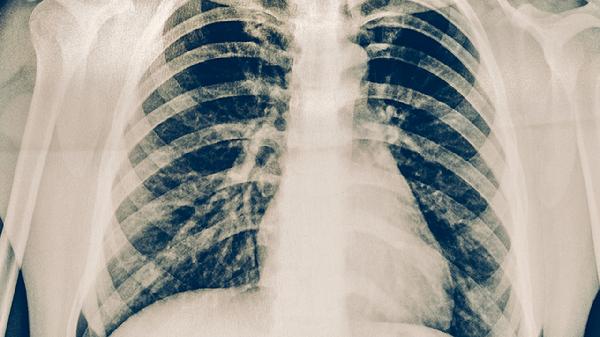

肺结核患者可通过适量增加优质蛋白摄入、补充维生素A和维生素C、选择易消化食物、避免辛辣刺激食物、保持规律饮食等方式进行饮食护理。肺结核是由结核分枝杆菌感染引起的慢性传染病,合理饮食有助于增强免疫力并促进康复。

肺结核患者除饮食调理外,需保证每日饮水1500-2000毫升,采用少量多餐制避免过饱。建议每周进行3-5次低强度有氧运动如散步、太极拳,运动时长控制在30分钟内。严格遵医嘱完成6-8个月抗结核药物治疗,定期复查胸部影像学。出现食欲显著下降或体重减轻超过5%时应及时复诊调整营养方案。